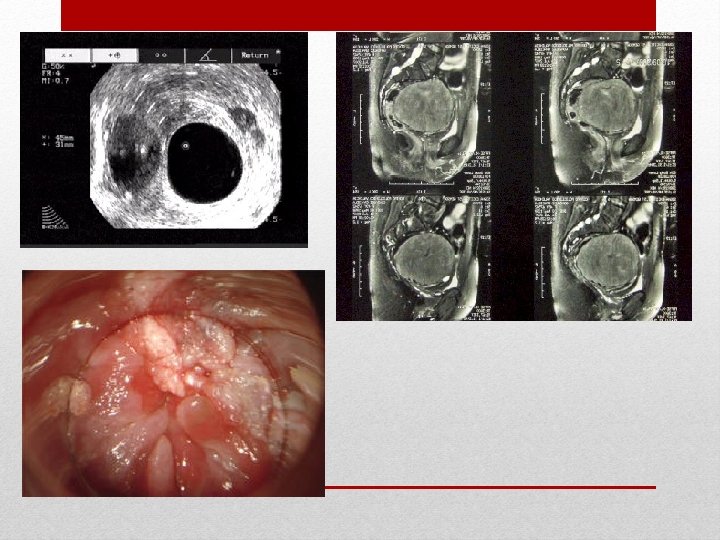

Estudios

• EE 2 tiempos • Múltiples sedales varias cirugías con intervalo de 15 días Tratamiento